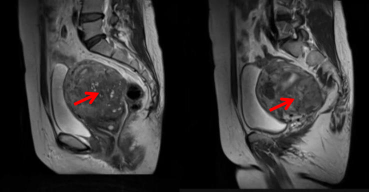

子宫腺肌病是子宫内膜腺体和间质异常侵入子宫肌层形成的疾病。简单来说就是子宫内膜跑到不该去的地方,钻到子宫肌层里面去了。子宫壁里面长出一些不该有的内膜组织,让子宫壁变厚变硬,就会出现各种症状,如痛经、月经量多、不孕等等。

子宫腺肌病病灶切除术为渴望保留子宫的患者提供了全新的治疗途径。该方案不仅能够精准地去除病灶区域,有效缓解相关症状,更重要的是,它尊重并保护了女性的子宫,满足了患者的特殊需求。

子宫腺肌病病灶切除术通过直接去除病灶组织,能够迅速达到治疗目的。不仅有效降低了术后的复发风险,还保留了子宫器官的完整性,使得患者在短期内即可观察到显著的症状改善。